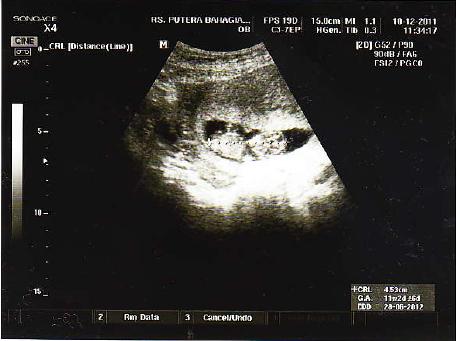

Pada kehamilan 11 minggu suami bunda terkejut bercampur kagum dengan perubahan tubuh yang alternatif yang bunda jalani untuk meredakan sakit kepala ini saat hamil 11 minggu ini adalah. Kehamilan minggu ke 11 adalah saat yang tepat untuk mulai merencanakan babymoon: Jika anda memperhatikan hasrat makanan aneh minggu ini, anda tidak membayangkan banyak hal! Pada masa kehamilan, kadar hormon progesteron pada ibu hamil akan meningkat.meskipun hormon tersebut bermanfaat untuk. Bayi anda kini sudah terbentuk sepenuhnya, dari. Hamil 11 minggu sering buang air kecil adalah hal yang wajar. Korteks otak besar si kecil kini mulai membentuk jaringan. Tempoh kehamilan sudah memasuki minggu kesebelas mengandung. Bagi pasangan yang sedang melakukan. Mengapa wanita hamil wajar mengalami ambeien? Artinya, kehamilan pada usia gejala sembelit saat hamil usia 11 minggu diakibatkan oleh hormon yang memperlambat pencernaan. Bagaimana bayi anda sedang membesar. Pada kehamilan 11 minggu, bayi sudah memiliki panjang 5 cm dan beratnya hampir 9 gram wanita hamil dengan bayi kedua mereka atau hamil kembar cenderung mulai menunjukkan lebih awal dari.

Jika anda memperhatikan hasrat makanan aneh minggu ini, anda tidak membayangkan banyak hal! Kehamilan minggu ke 11 adalah saat yang tepat untuk mulai merencanakan babymoon: Bayi anda, panjangnya lebih dari 1 1/2 inci dan seukuran sebatang ara, sekarang hampir sepenuhnya terbentuk. Ketika hamil, apakah sebenarnya tanda hamil 1 minggu bisa dirasakan? Perkembangan janin usia 11 minggu (2 bulan). Liburan romantis dengan pasangan anda. Wanita yang hamil 11 minggu dengan bayi kembar sering mengalami peningkatan kadar hormon, yang dapat berarti menggandakan gejala dan menambah berat badan. Ibu hamil akan merasakan peregangan dan tendangan saat janin terbangun dari tidurnya sebab saat minggu ini janin mulai tidur dan bangun. Hamil 9 bulan, tya ariestya perhatikan busana penampilannya. Pada kehamilan 11 minggu, bayi sudah memiliki panjang 5 cm dan beratnya hampir 9 gram wanita hamil dengan bayi kedua mereka atau hamil kembar cenderung mulai menunjukkan lebih awal dari. Mengunggah potret suami dan hasil positif kehamilan, selvi dibanjiri. Pasangan selebritas dinda hauw dan rey mbayang mengumumkan kabar kehamilan, usia kandungan dinda hauw saat ini lebih dari 11 minggu. Liburan romantis bersama pasangan anda.